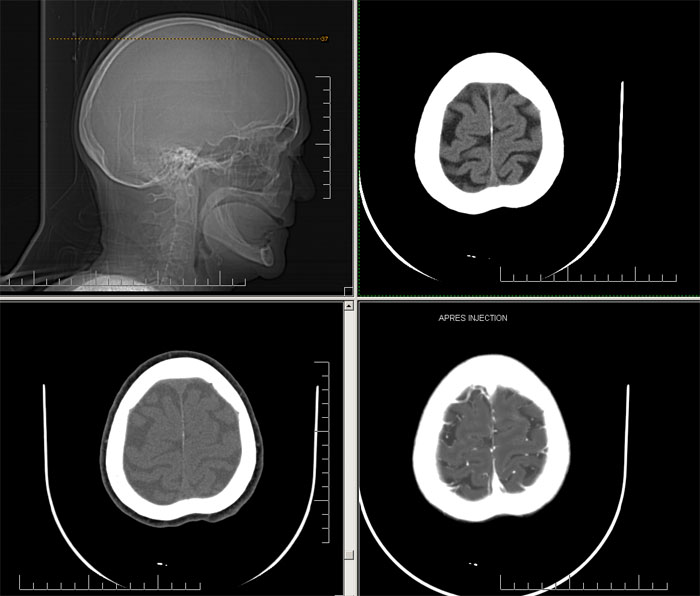

Est ce que qqun a des coupes axiales de crâne pour m'aider à réviser mon anatomie. Merci

Pour compléter tes révisions, Poupette vient de nous faire parvenir ces planches bien utiles: Planches de coupes axiales cérébrales, dans la rubrique COURS / ANATOMIE